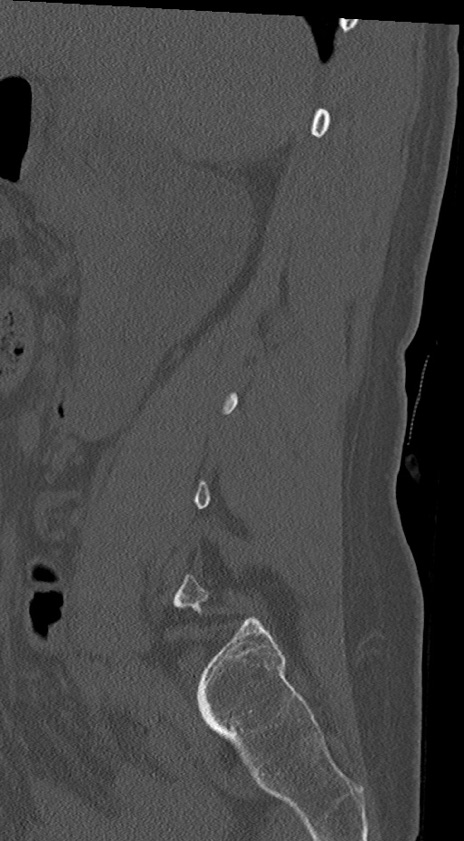

【整形】TIPS症例4 腰椎CT(矢状断像)

腰椎CT

冠状断像